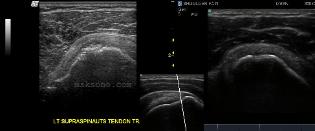

Right: 17yr old football player injured

shoulder after reaching for a fumble.

While reaching above his head, his arm

was also pulled back behind him.

This image is axial to the body plane,

long axis to the Subscapularis tendon,

and just lateral to the coracoid process.

The Biceps groove in this image is

located just to the right of the text on

the image.  It is filled with the

surrounding connective tissues, and

part of the transverse humeral ligament.

CLICK ON IMAGE TO SEE MORE OF

THIS CASE STUDY.